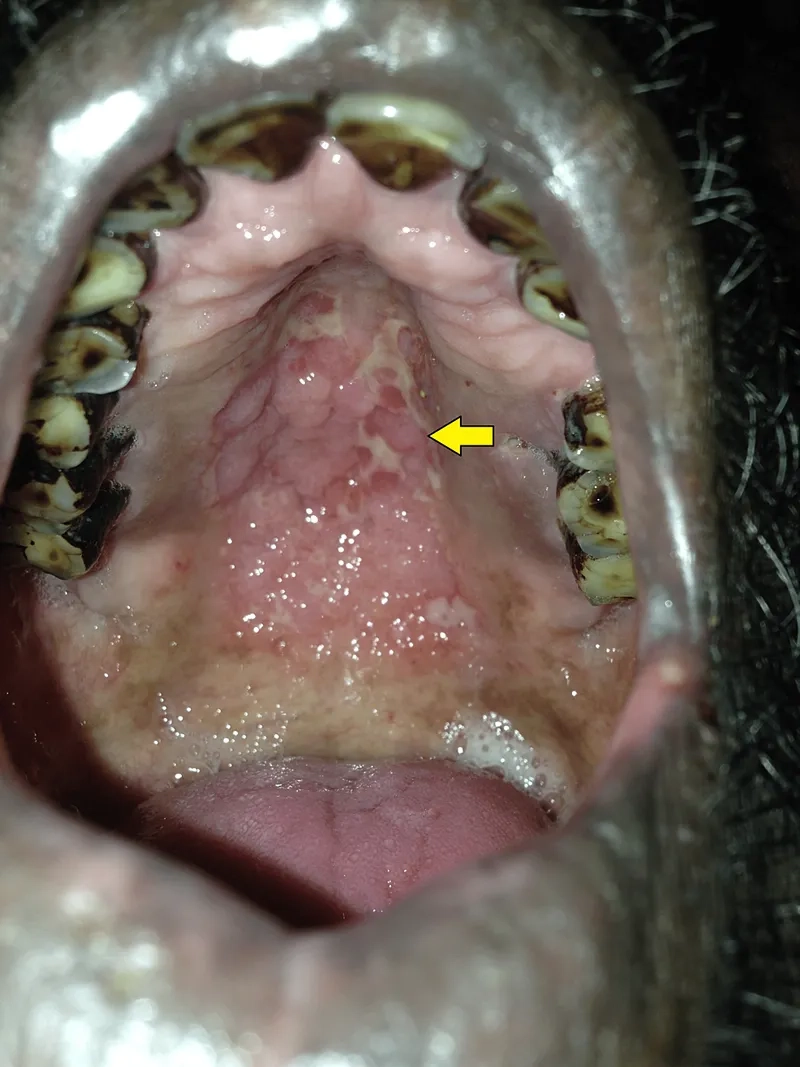

Pictures of Histoplasmosis